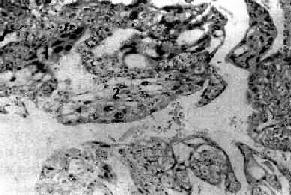

镜下,成片增生及分化不良的滋养层细胞侵入肌层和血管。瘤组织由分化不良的两种滋养层细胞组成,即细胞滋养细胞和合体滋养细胞。细胞滋养细胞胞浆丰富、淡染,细胞境界清楚,核空泡状。合体滋养细胞体积大、胞浆红染并互相融合,核椭圆形。这两种细胞排列紊乱(图13-13)。不同肿瘤中这两种细胞所占比例不同,有的以细胞滋养细胞为主,有的以合体滋养细胞为主。核分裂像常见。绒癌组织无间质,常呈广泛出血坏死,不形成绒毛结构。如发现有绒毛,即使是退化的绒毛,也应诊断为侵蚀性葡萄胎。

图13-13 绒毛膜癌

癌组织没有间质,癌巢由于两种细胞组成:1.合体细胞样细胞;2.细胞滋养层细胞样细胞